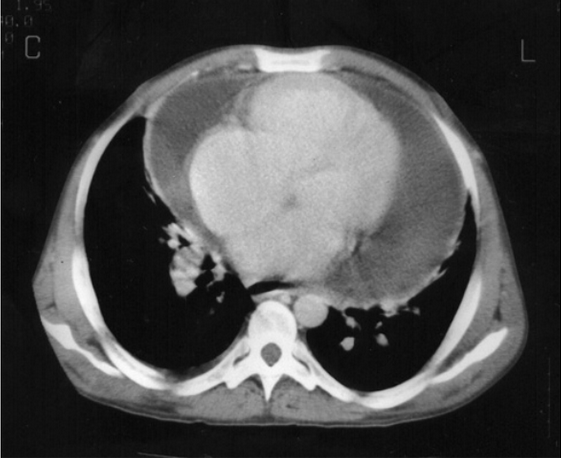

péricardite tuberculeuse.png